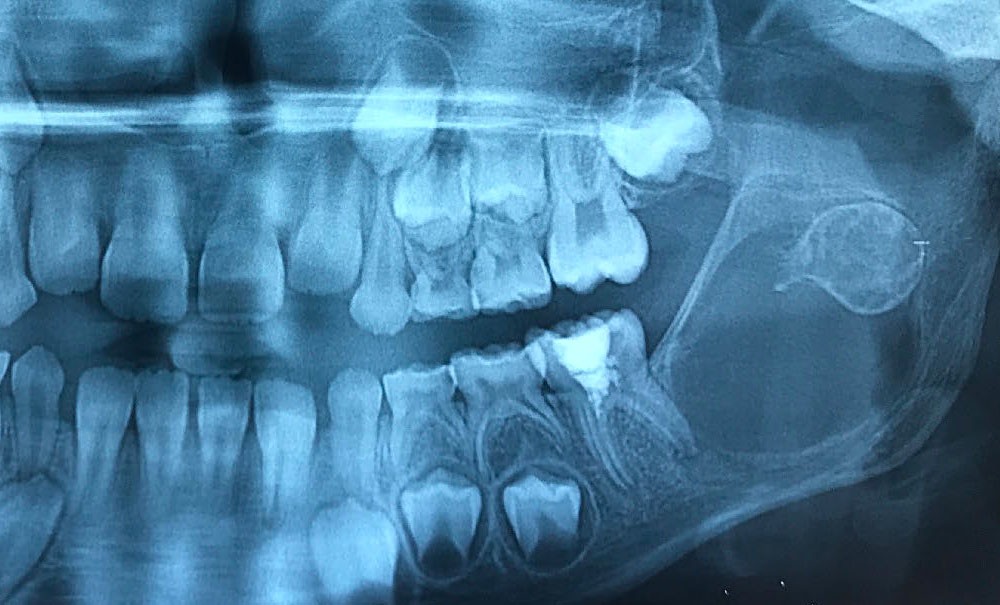

Les kystes et tumeurs bénignes osseuses maxillaires ou mandibulaires chez l’enfant sont le plus souvent asymptomatiques. Ces lésions osseuses sont découvertes de façon fortuite lors d’un bilan radiographique de routine réalisé par l’odontologiste pédiatrique ou l’orthodontiste [1-3]. Néanmoins, des lésions peuvent parfois se développer rapidement et être destructrices [1, 2]. Certains signes cliniques spécifiques à la chronologie de l’éruption dentaire chez l’enfant doivent nous alerter tels qu’un retard d’éruption dentaire ou une éruption dentaire asymétrique (fig. 1). D’autres manifestations cliniques, moins spécifiques à l’enfant, peuvent également orienter le clinicien sur la présence d’une pathologie osseuse sous-jacente : mobilité dentaire, douleur, tuméfaction, limitation de l’ouverture buccale, trouble neurosensoriel, etc. [3]. C’est la radiographie panoramique qui va ensuite mettre en évidence/confirmer la présence d’une lésion intra-osseuse (fig. 2).

La radiographie panoramique permet une première interprétation de la lésion osseuse (localisation, nombre, taille approximative, etc.). Cet examen est souvent complété par un bilan d’imagerie en trois dimensions de type Cone Beam [4]. Il précisera le volume et les limites de la lésion ainsi que ses rapports avec les structures anatomiques avoisinantes (tableau 1). Ces données radiologiques confrontées à l’examen clinique et à la fréquence relative des lésions permettent de réaliser un diagnostic d’intuition qui orientera la prise en charge.